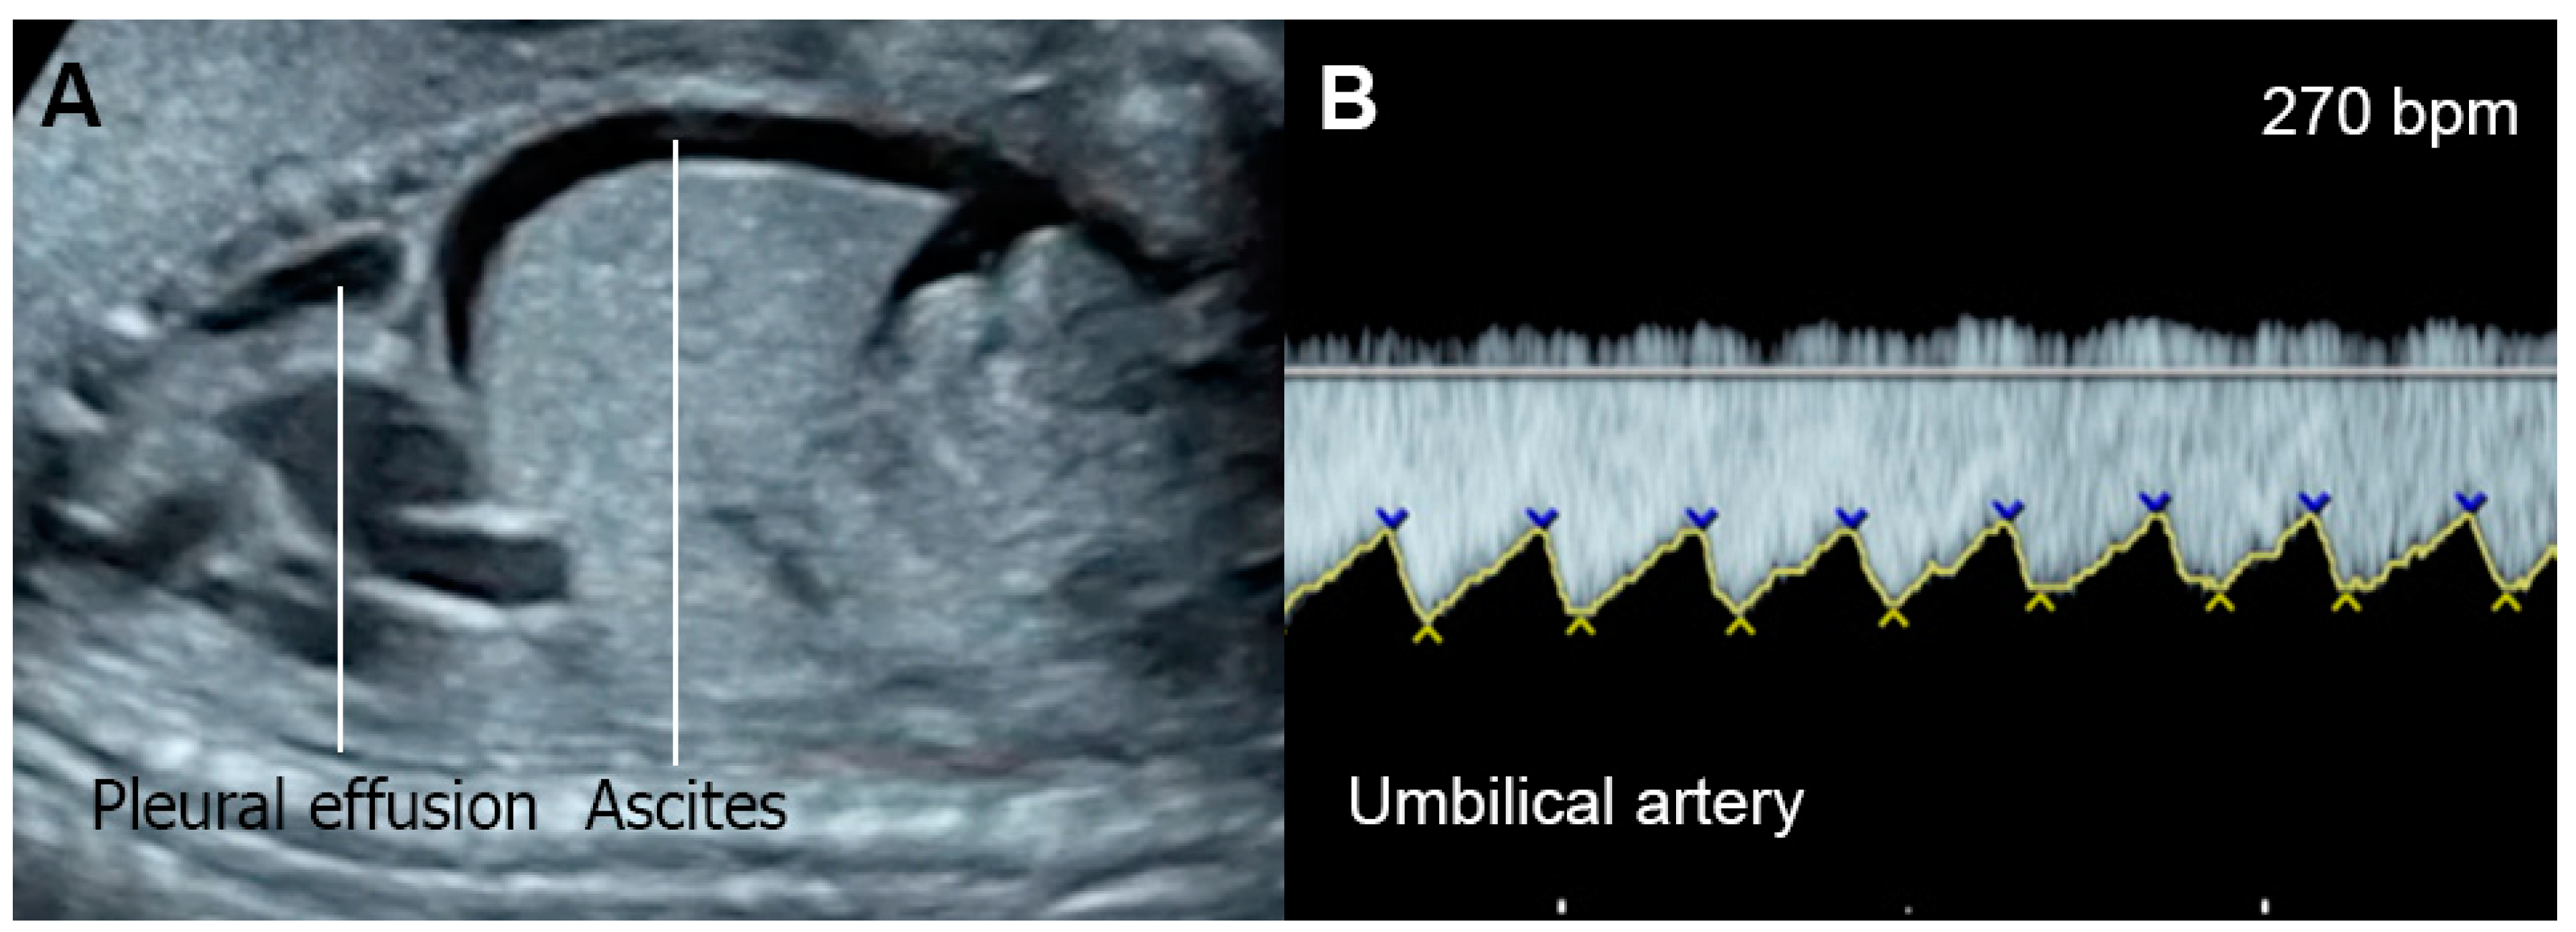

- Supraventricular tachycardia and atrial flutter; the most common causes in this group, usually associated with tachycardia of greater than 220 bpm

- Gembruch, U.; Krapp, M.; Baumann, P. Changes of venous blood flow velocity waveforms in fetuses with supraventricular tachycardia. Ultrasound Obstet. Gynecol. 1995, 5, 394–399. [Google Scholar] [CrossRef]

- Naheed, Z.J.; Strasburger, J.F.; Deal, B.J.; Benson, D.W., Jr.; Gidding, S.S. Fetal tachycardia: Mechanisms and predictors of hydrops fetalis. J. Am. Coll. Cardiol. 1996, 27, 1736–1740. [Google Scholar] [CrossRef]